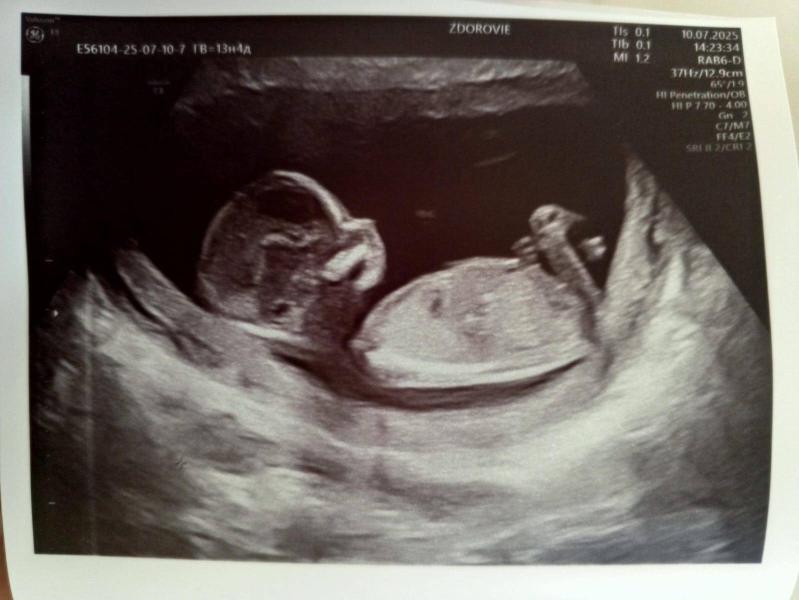

Врач предположила девочку на 99,9%

По крови же девочка 😁

Врач сказал ещё, что то ли расширение вен, то ли сосудов, что сосуды могут лопнуть и будет гематома, кровотечение

И ещё сказала на левом желудочке сердца белый шарик, гиперохогенное или анахогенное или что-то там. Не поняла ещё и забыла

Несколько знаю существует процедура УЗИ конкретно сердца плода. Я бы нашла хорошего спеца и сходила.

Краевое предлежание опасно отслойкой, тут витамины непричем. Берегите себя, не таскайте тяжести и тд